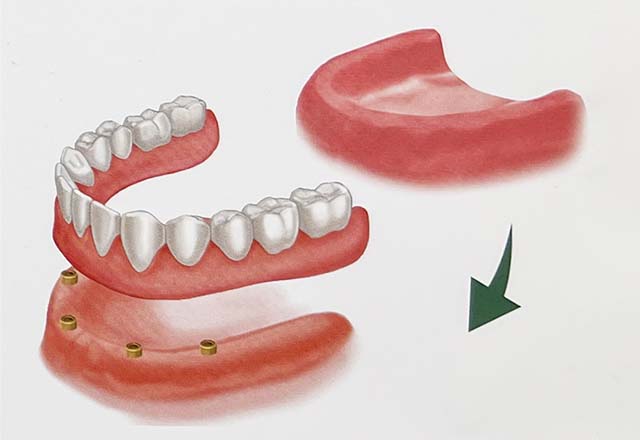

| 治療の説明 | 他院で抜歯を行った後、入れ歯を勧められましたが、入れ歯には抵抗があり、他の治療方法を探されていました。 その結果、当院でインプラント治療を希望されました。 患者様のご希望により、歯の欠損部分をインプラントで補い、上部構造(被せ物)にはフルジルコニアセラミックのブリッジを選択されました。 そのため、見た目や噛み心地がより天然歯に近い仕上がりとなりました。 |